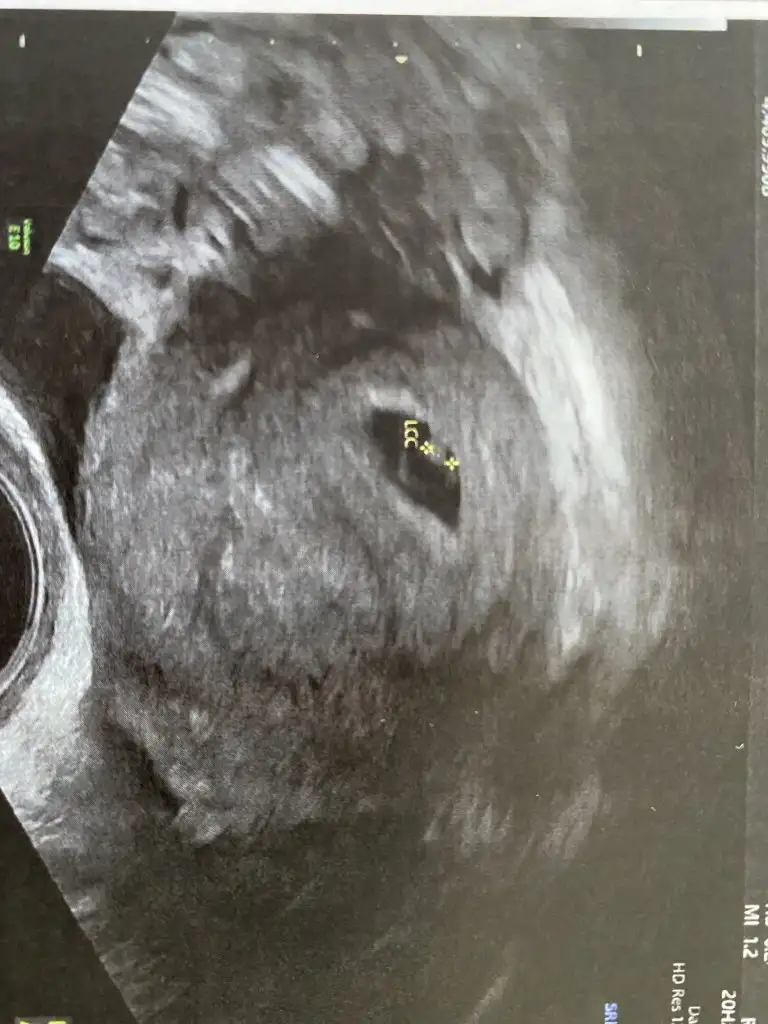

Ben dun hamile olduğumu ögrendim, kese göründü ve beta hcg 1640 cikti, bugün yine baktirdim, yani 24 saat sonra 2054,8 cikti… sizce normal mi? Veya düsük mu yapıyorum?

Evet. Keseyi de gördük. Bebeği de gördük çok şükür. darısı sana inşallahSizde benim gibi 5 haftalik hamilesiniz, hayirli olsunKeseyi gördunuz mu?